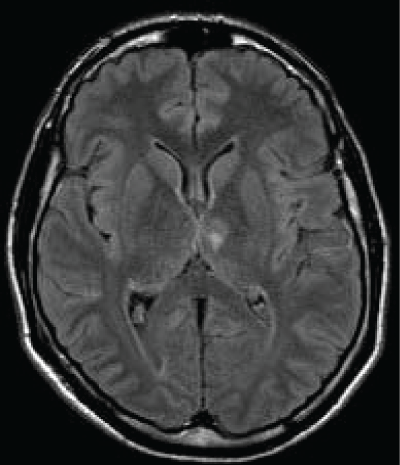

A 45 years old Caucasian male was admitted to our Neurological Clinic for a sudden onset of visual impairment and pure horizontal diplopia, disequilibrium and left lateropulsion. While he was coming to hospital he noted also a speech disorder (mainly referred as word-finding difficulties, reduced fluency, denomination and writing disorders). At admission cerebral CT and angio-CT was performed but no lesions were seen, neither vessels abnormalities. During hospitalization antiplatelet therapy was started. Patient performed screening vascular examination including echocardiography carotid Doppler and thrombophylic screening tests. Soon dizziness and visual disorder ameliorated but then he showed palipsychism (which corresponds to an overlap of sequential cognitive processes in two or more domains); patient also showed severe perseverative behavior with increased sensitivity to interference, anterograde memory retrieval deficit with memory loss and produced a decreased and invalid-output speech, characterized by unpredictable topic shifts, with grammatically correct phrases, sometimes he accused naming difficulties and apathy with affective flatness. Moreover he accused some kind of stiffness on both his upper arms. Neuropsychological tests were performed showing preservation in performing automatic series and executive functions, and a "transcortical sensitive-aphasia-like speech disorder". After a few days cerebral magnetic resonance was performed, it showed a thalamic ischemia in the paramedian left thalamic nuclei territory (Figure 1 and Figure 2); as a result of a possible cardioembolic stroke.

As we said the fluid-attenuated inversion recovery (FLAIR) and T2 MRI revealed a hyperintense lesion (hypointense in T1 sequences) compatible with a left paramedian thalamic infarction in a patient with onset of confusion, confabulation, and memory impairment (Figure 3). Patient was discharged at home but he felt not to be confident to live alone anymore.